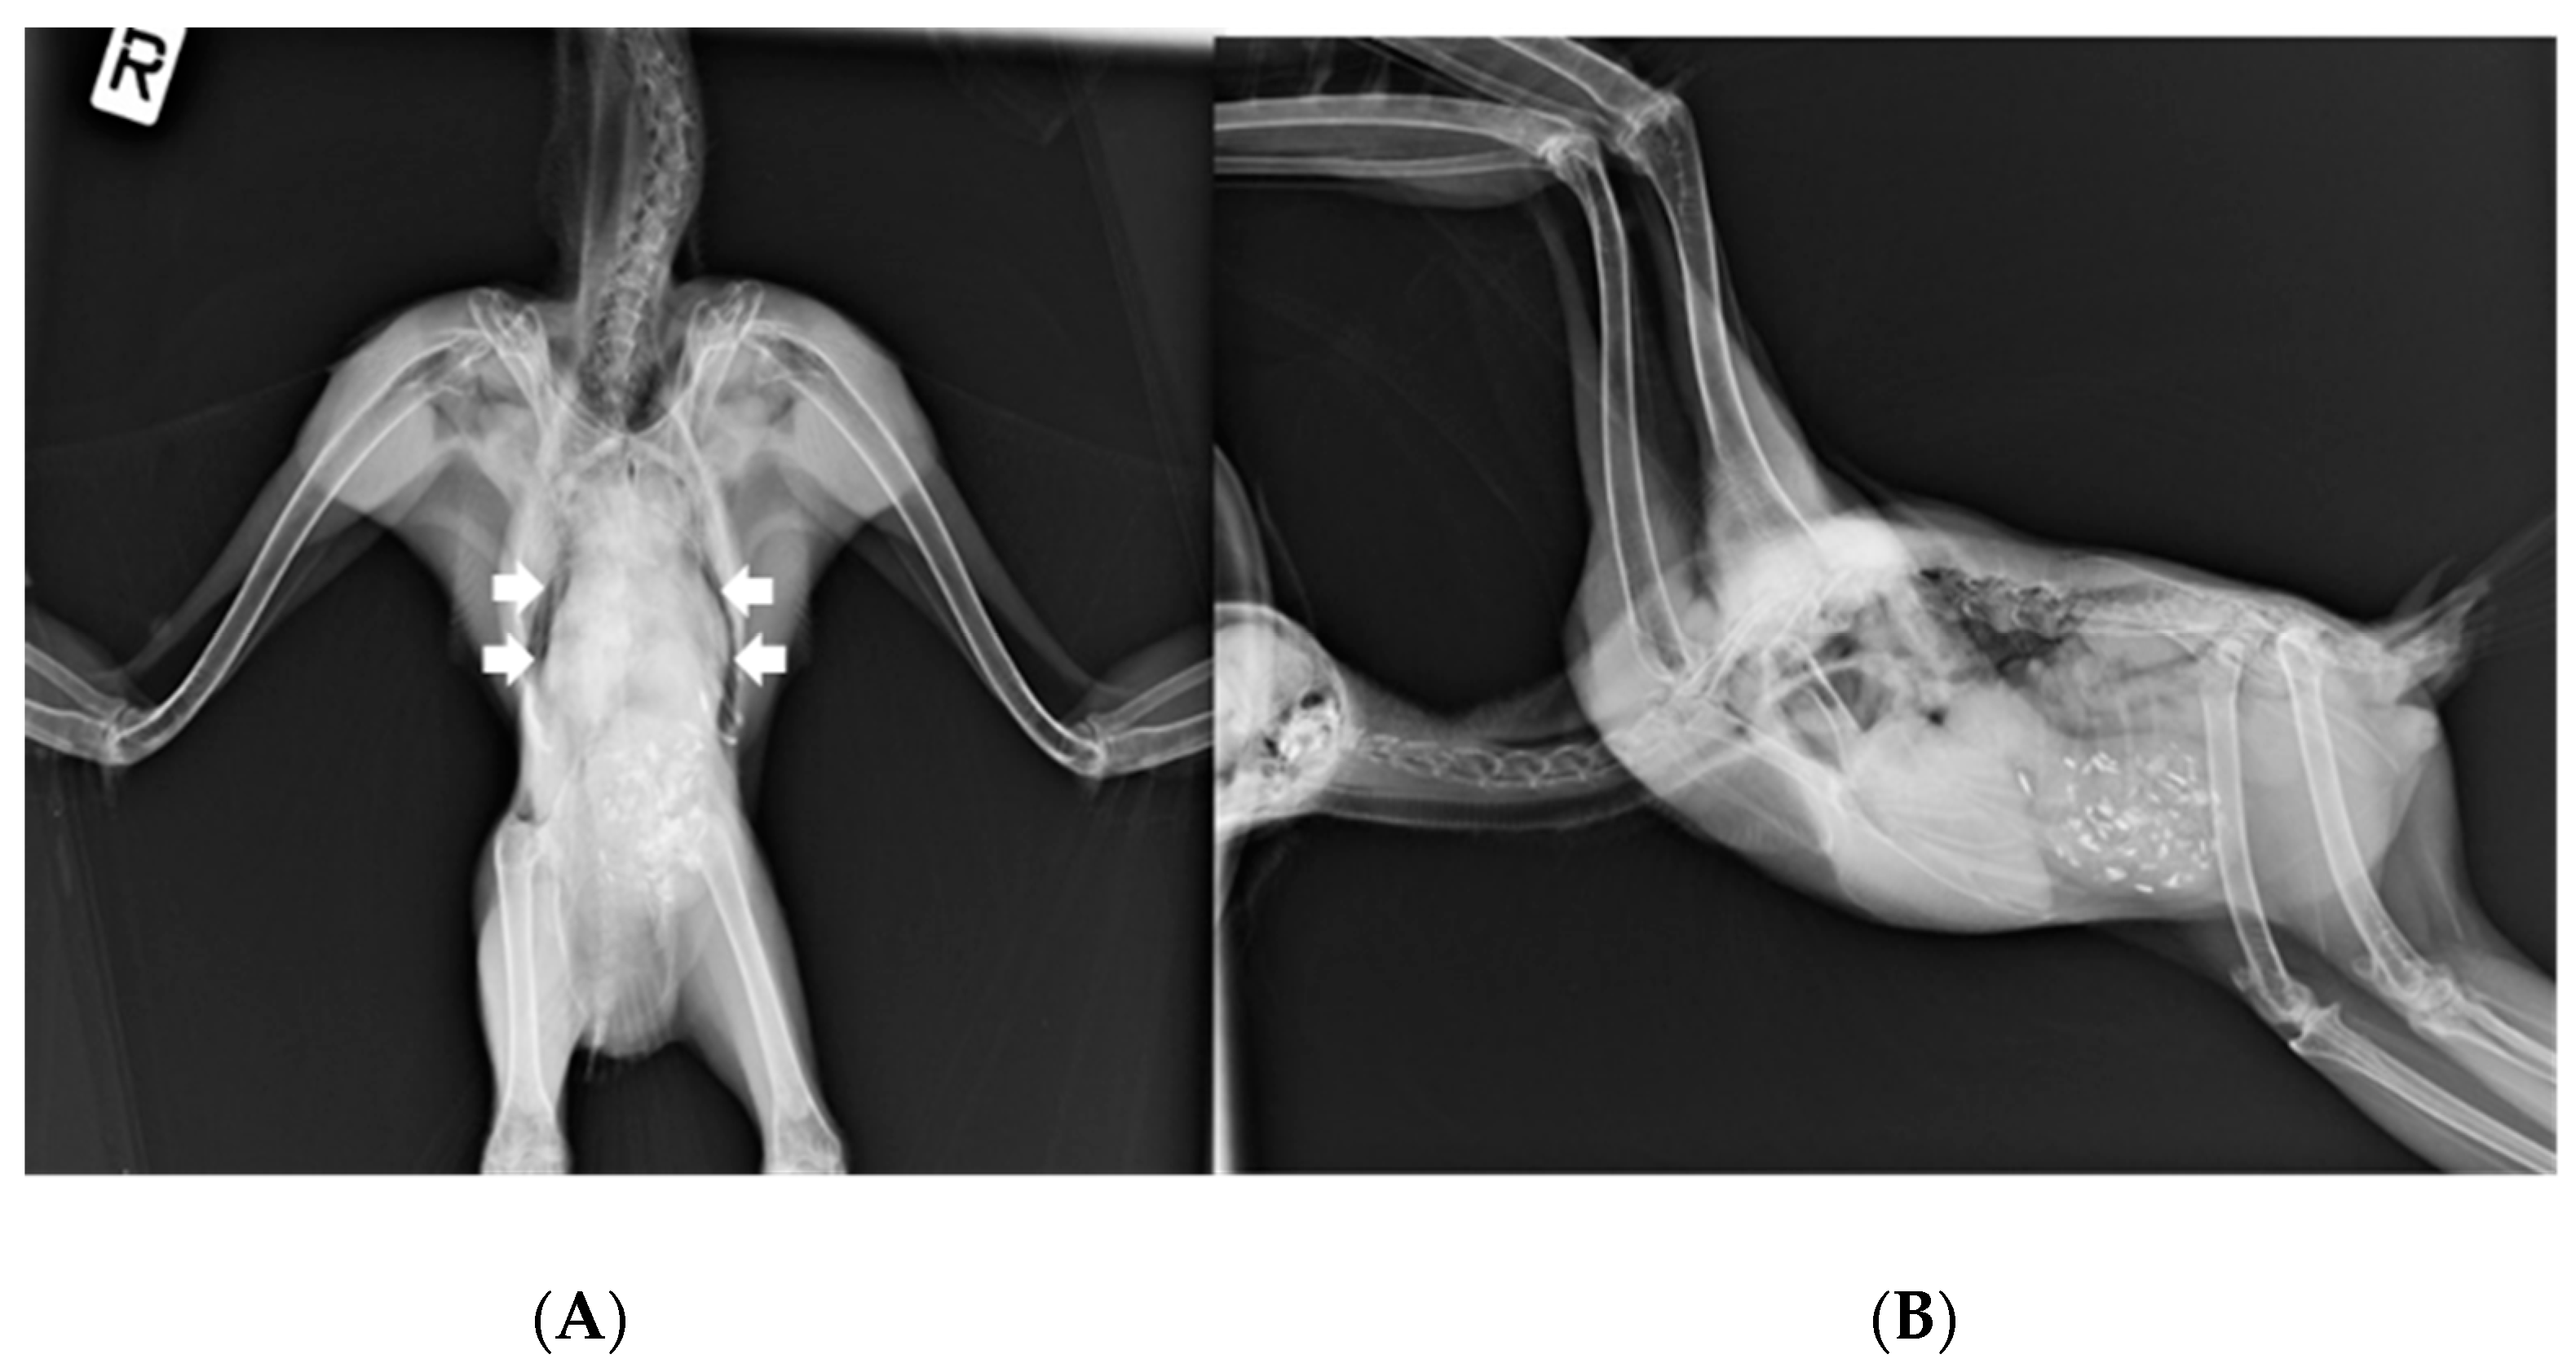

On 15 March, the owl’s weight was 1115 g. Ventrodorsal and right lateral radiographic images (Figure 2) under general anesthesia (3% isoflurane in a 1.5 L flow of oxygen with a facemask) revealed a widened cardiohepatic waist, and oropharyngeal swabs were positive for HV presence. Subcutaneous Ringer’s solution and vitamins A, D3, and E (Krka, Novo Mesto, Slovenia) were administered.

The great grey owl, despite a 6-month period of HV detection in oropharyngeal and cloacal swabs, showed no clinical signs of disease, nor did histopathological findings show any changes that could possibly be related to HV infection, such as intranuclear eosinophilic inclusion bodies in hepatocytes and necrosis of the liver and spleen. Ventrodorsal radiographic images revealed a widened cardiohepatic waist, which could indicate hepatomegaly due to herpesvirus infection. However, it should be emphasized that the general rule an “hourglass”-shaped junction between the heart and liver does not apply to raptors, in which a commonly much wider cardiohepatic waist and poorly defined junction between the heart and liver are observed. Other possible reasons for the extension of the lateral edges of the liver could be proventricular enlargement (due to disease or due to a full GI tract) or a mass in the coelomic cavity [23]. The phylogenetic analysis of the HV DNA polymerase sequence detected in the great grey owl showed a high similarity (99%) with the HV DNA polymerase sequence detected in a free-living Ural owl found dead [11], an injured long-eared owl [24], and a live free-living Ural owl, which showed no clinical signs of illness or productivity (i.e., clutch or brood size) deviances [5] (Figure 1). To the best of our knowledge, this is the first report of HV presence in a great grey owl, so the exact impact on this species is unknown; however, based on no recorded clinical sign of illness in this study and the high similarity with the sequence detected in a closely related clinically healthy Ural owl, we could assume that the detected HV has little or no impact on the great grey owl. Nevertheless, such an HV-infected great grey owl represents a possible source of infection for other owls and birds, especially in shared and/or smaller places, such as zoos. HVs are not always restricted to a specific host or tissue, and crossing host or tissue barriers can considerably alter the pathogenicity of the virus [3]. In consideration of this, antiviral therapy with acyclovir was used to reduce the likelihood of HV transmission and potential pathogenicity in other birds. Acyclovir is the first-line treatment for herpes simplex (HSV-1, HSV-2, and VZV) in humans [25]. In birds, some effectiveness has been shown in treatment and prophylaxis for Pacheco’s disease; however, limited data are available for the dosage and use of acyclovir in HV treatment in birds. The treatment/prophylaxis dose depends on the causative agent and on the species of the bird being treated [26,27].

Figure 2. (A) Ventrodorsal and (B) right lateral radiographic images of the male great grey owl showing widened cardiohepatic waist (marked with white arrows). The “R” mark (image (A)) indicates the right side of the body.